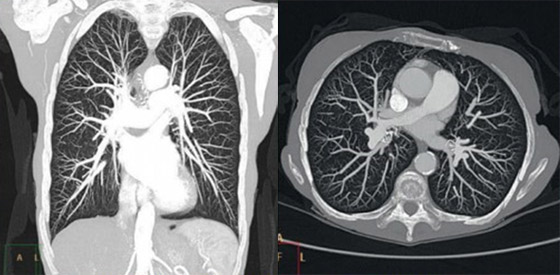

With a SmartPath upgrade you can benefit from our advanced reconstruction technology – IMR, or iterative model reconstruction.

IMR allows you to combine virtually noise-free images and industry-leading low-contrast resolution with significantly lower doses[1]. And reconstruction time for the majority of reference protocols is less than 3 minutes*.

Together iDose4 and O-MAR produce high image quality with reduced artifacts

iDose4 Premium Package is an innovative solution that helps you personalize image quality based on your patients’ needs at low dose.

iDose4 improves image quality* through artifact prevention and increased spatial resolution at low dose. It provides a unique approach to managing important factors in patient care – low energy, low dose, and low injected contrast imaging.

O-MAR reduces artifacts caused by large orthopedic implants. Together they produce high image quality with reduced artifacts for increased diagnostic confidence. In fact the majority of our reference protocols can be reconstructed in less than one minute.